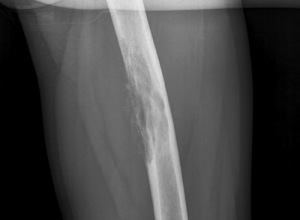

Рентгенологическое исследование является главным методом, который позволяет определить протяженность и локализацию пораженного очага. С помощью рентгена можно установить патологоанатомические изменения. Большую ценность представляет и томография. Всем пациентам, у которых выявлена свищевая форма заболевания, делают фистулографию. Этот метод основан на введении рентгеноконтрастного вещества в пораженную костную полость через свищевой ход. Затем выполняется рентгенография в двух проекциях. Точная пораженная зона определяется с помощью радиоактивного сканирования, при котором применяется радиоактивный технеций. С помощью этого можно решить вопрос об операции.

Хронический остеомиелит на рентгенограммах проявляется гиперостозом (и, как следствие, деформацией кости), очагами деструкции кости, окружёнными зоной склероза, секвестрами, остеопорозом. Фистулографию используют для диагностики свищей между полостями деструкции и мягкими тканями.